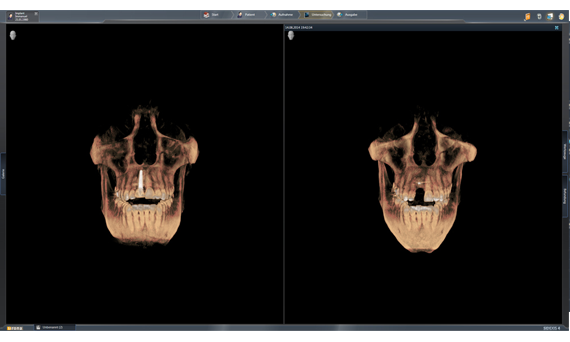

在灯箱中,您可以同时比较2D和3D图像、内窥镜画面和面阵扫描数据。

Sidexis 4数字灯箱灵活性强,可在软件界面上无缝显示所有图像类型。所有2D、3D和口内图像都可以同时处理和查看,以确保所有图像数据都可用于诊断过程。例如,可以对口内图像和3D扫描进行快速确切的交叉比较,从而极大简化诊断和治疗计划过程。因此,从患者咨询到治疗计划和模拟,这款直观的软件为您的诊断提供了理想的条件。

作为一个用户,您可能会问为什么此工具不总是实用,其实“比较”功能在软件中很有用:在比较窗口中,可以同时评估多个图像。